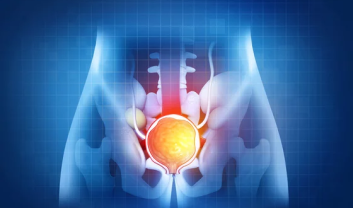

Urinary bladder stones, also known as vesical calculi, are crystallized formations that develop in the bladder....

Urinary bladder cancer is a formidable health challenge affecting individuals worldwide. As a complex and multifaceted condition...